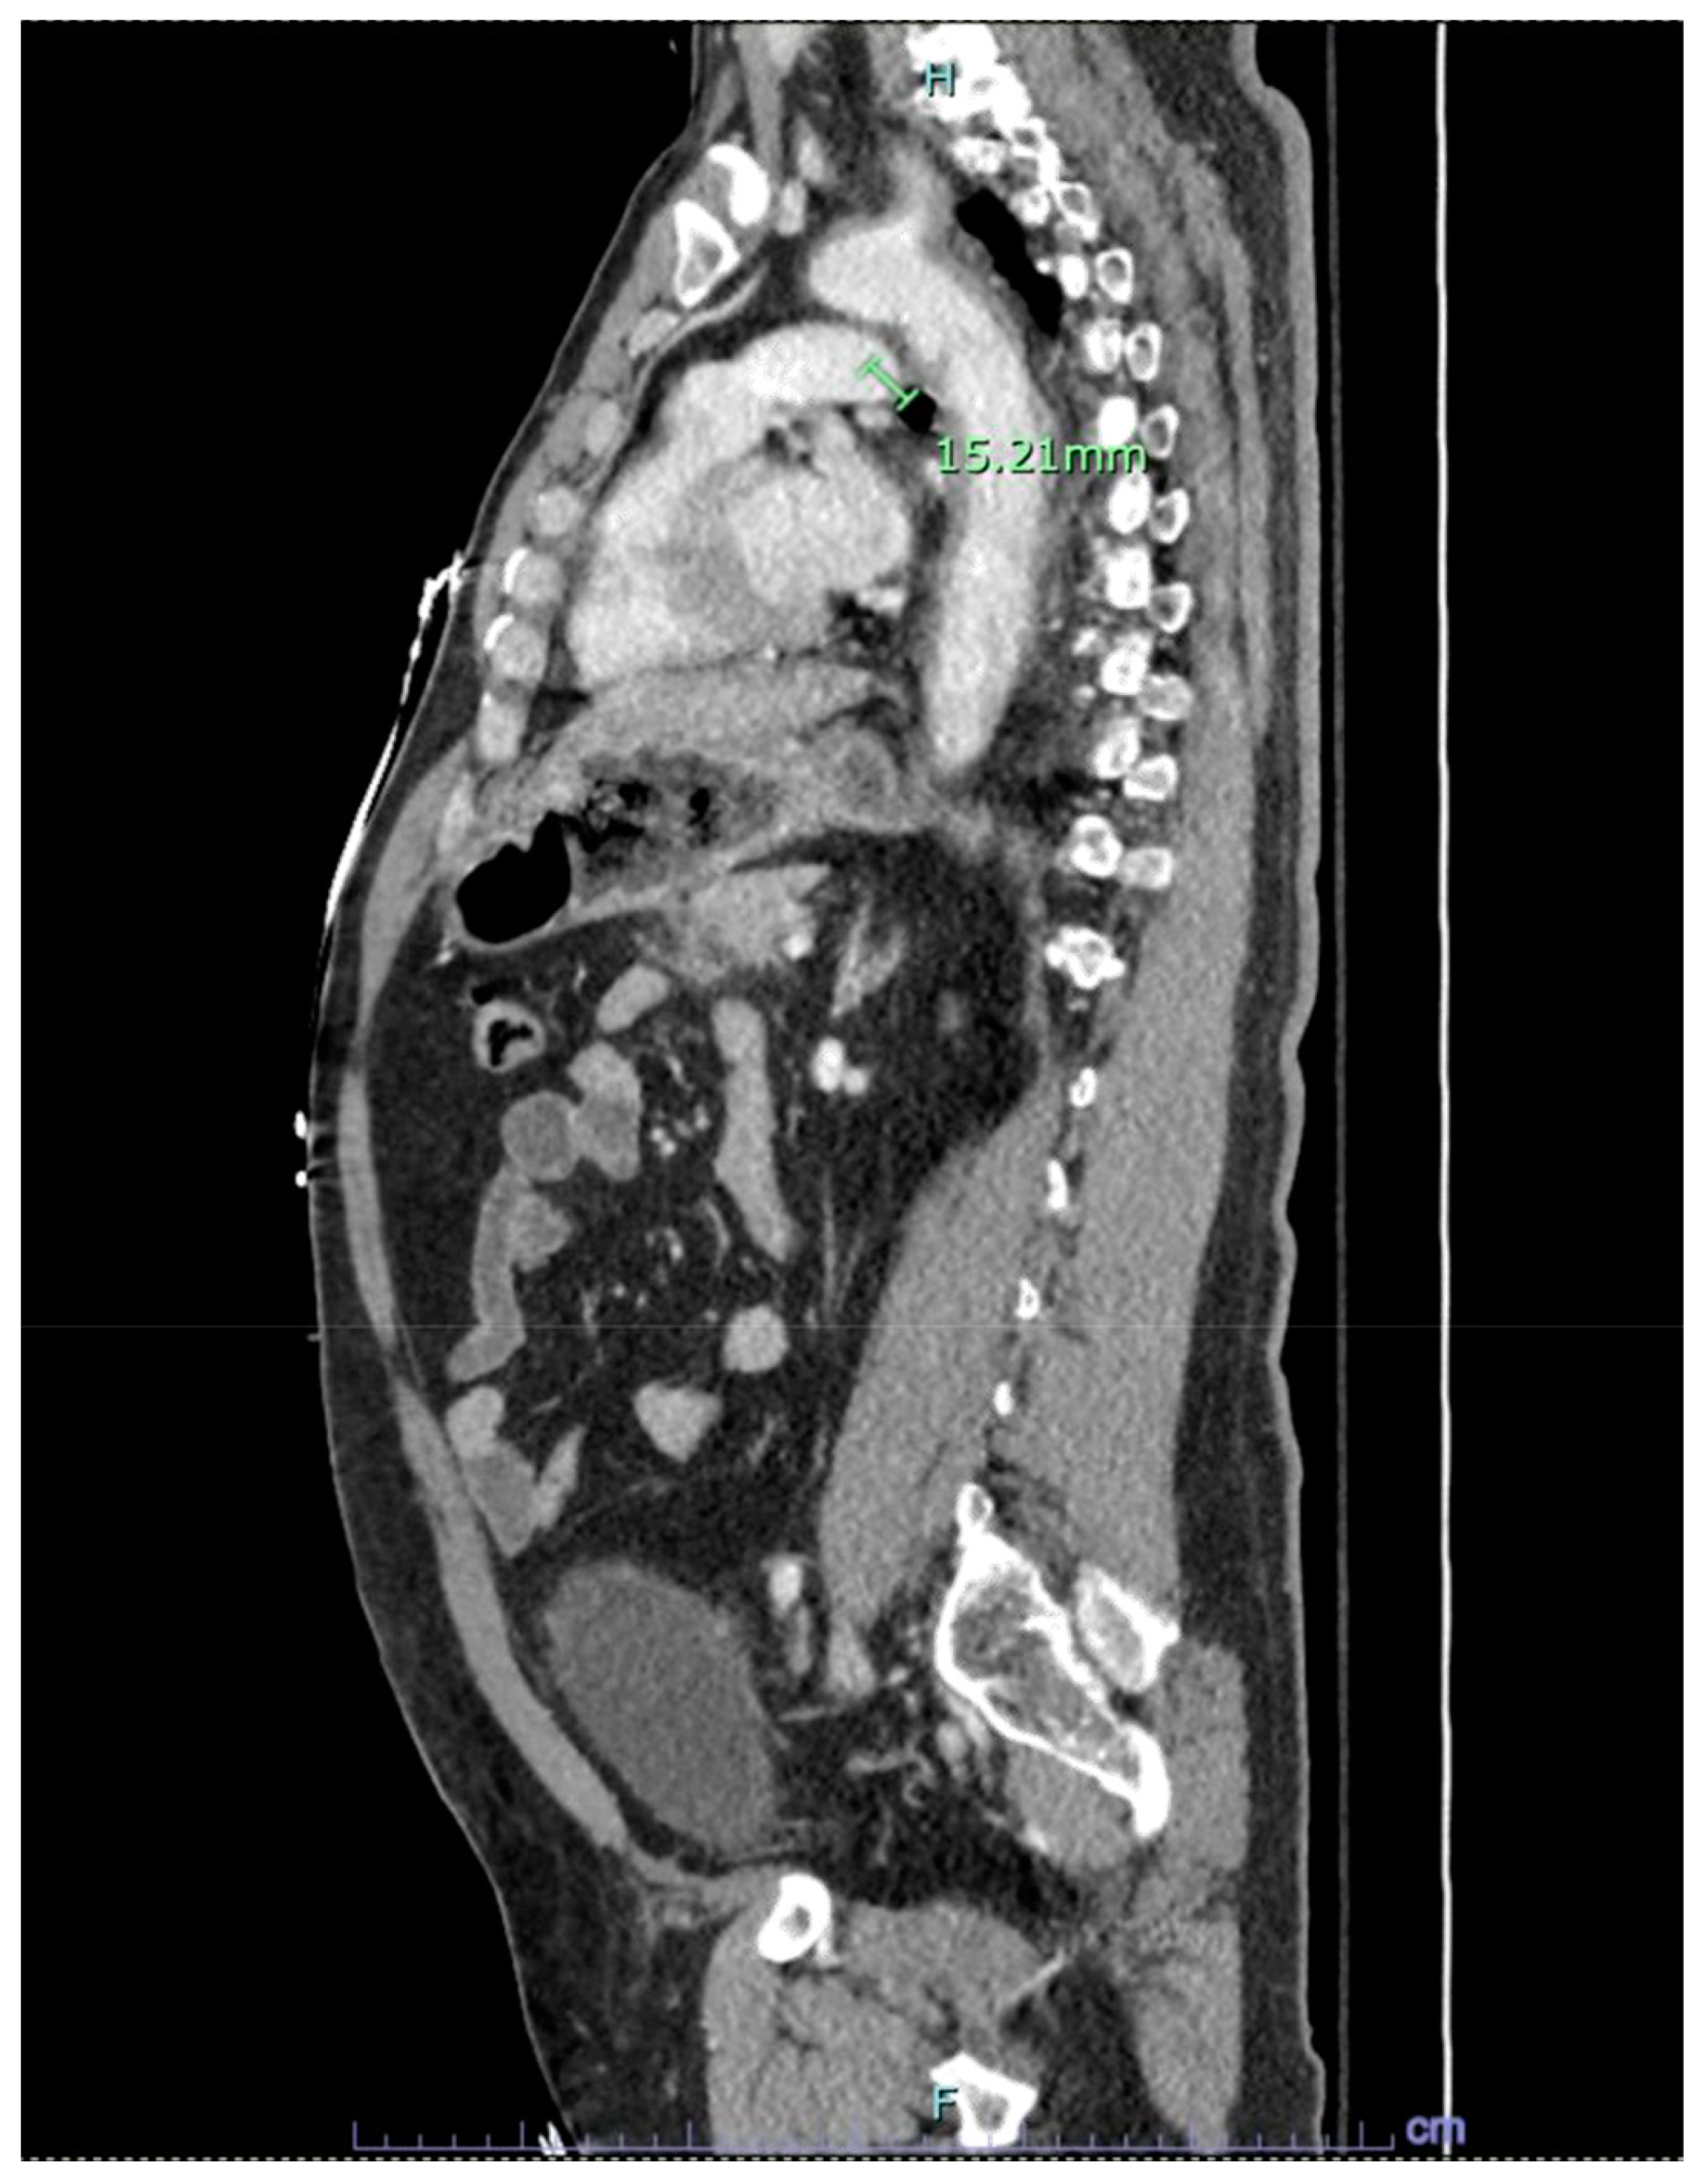

Figure 3. CT scan revealing a flap coursing across the medial wall of descending aorta with an associated pseudoaneurysm of size 1.5cm protruding anteromedially.